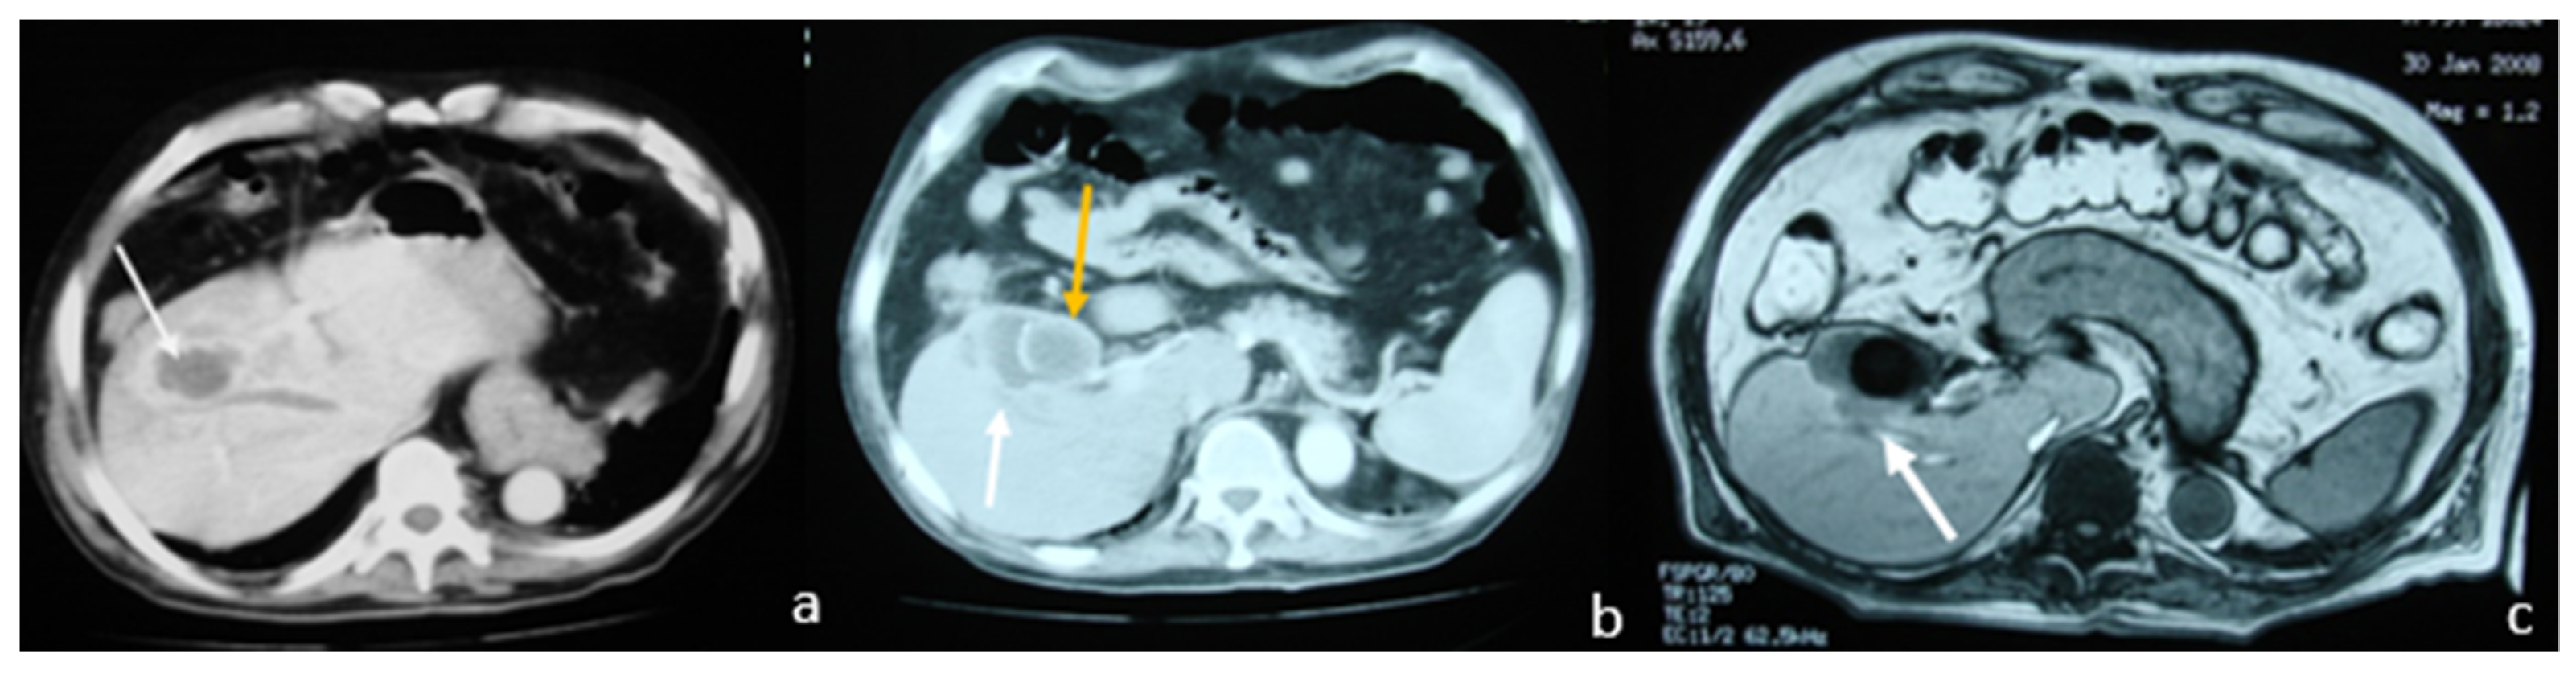

2.1. Case 1

2.2. Case 2

2.3. Case 3